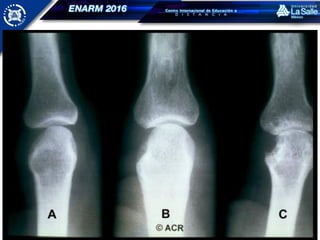

RADIOLOGÍA

Radiología simple - convencional

CAMBIOS RADIOLÓGICOS

Aumento de volumen de los tejidos blandos,

fusiforme y generalmente simétrico

Osteopenia yuxtaarticular

Disminución simétrica del espacio articular

Erosiones marginales del hueso subcondral

Pérdida de la alineación

Deformidades

ARTRITIS REUMATOIDE RADIOLOGÍA Radiología simple- convencional Ultrasonido TC IRM Artrografía

• 57.

ARTRITIS REUMATOIDE CAMBIOS RADIOLÓGICOS Aumentode volumen de los tejidos blandos, fusiforme y generalmente simétrico Osteopenia yuxtaarticular Disminución simétrica del espacio articular Erosiones marginales del hueso subcondral Pérdida de la alineación Deformidades